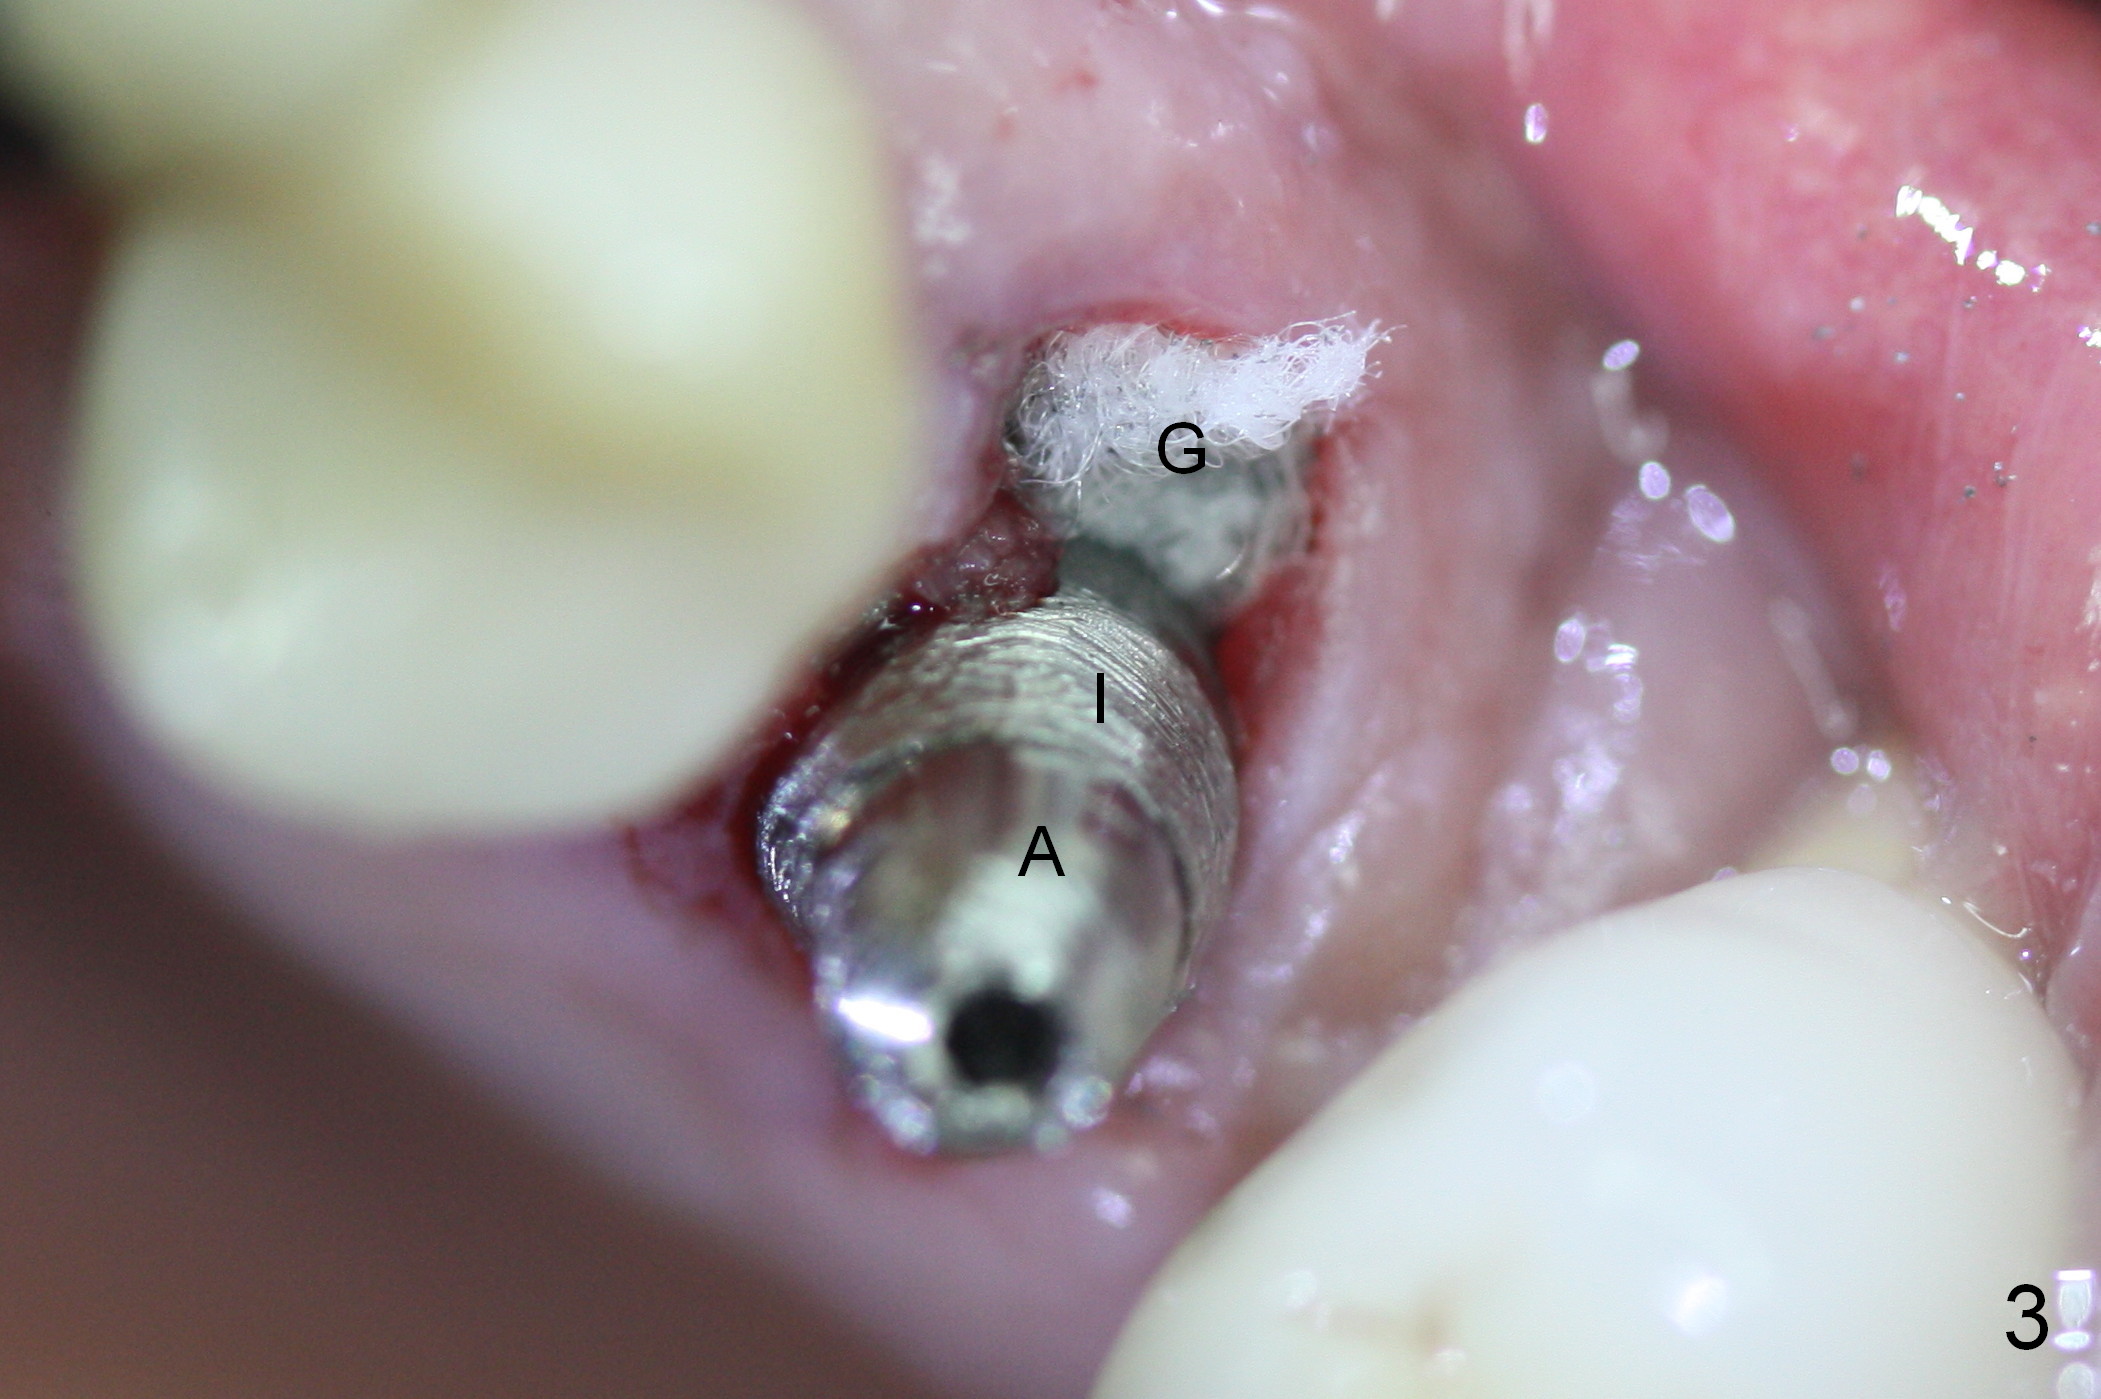

Extraction of the affected 2nd premolar is easy; the apical bone is so hard that drill and reamers have to be used for osteotomy, followed by insertion of a 4.5 mm tap with stability (Fig.1 T). The sinus floor (^) is lifted. There is no sign of sinus membrane perforation before placement of a 4.5x14 mm implant (Fig.2 I); sinus lift is performed (*: autogenous bone mixed with Mineralized Cancellous Human Allograft, Impladent); an immediate abutment (3.5x3 mm) is placed (A). With gauze placed in the buccal gap (Fig.3 G), the margin of the implant (I) is prepared for an immediate provisional fabrication. Mixture of autogenous bone (from reamers), allograft and Osteogen is placed in the remaining socket (Fig.4,5 *). When the relined (1st modification), trimmed and polished provisional is reseated (Fig.6 P), the bone graft (*) is not completely covered. New acrylic (2nd modification) is added to the margin of the provisional (Fig.7 *) for containment of the graft. There is almost no buccal plate; Osteotape (collagen membrane with Osteogen) is placed against the buccal wall of the socket prior to bone grafting. The remaining small pieces of the Osteotape (Fig.7 <) are laid over the bone graft before reseating the final provisional. With "complete socket seal", perio dressing is unnecessary.